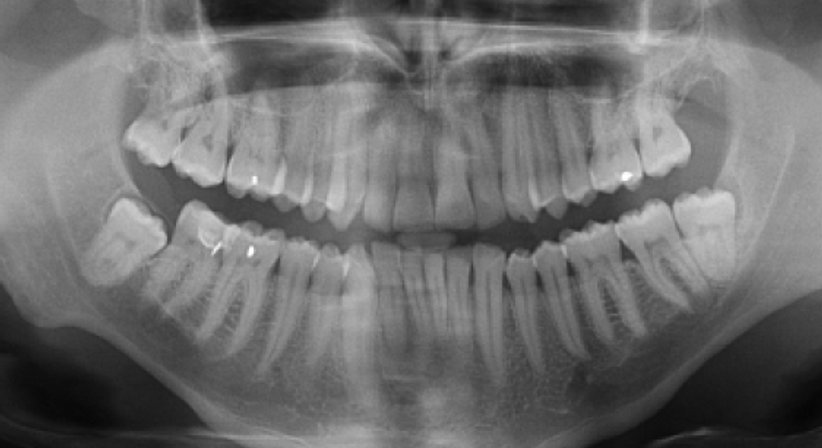

Dieses Gerät ermöglicht neben digitalen 2D-Zahnpanoramaaufnahmen mit variabler Fokuszonentechnologie auch die Durchführung von Aufnahmen mittels 3D-digitaler Volumentomographie (DVT).

• Planung von Zahnimplantaten

• Kiefer/Zahn Erkrankungen

• Kiefergelenke

• Nasennebenhöhlen

• Cephalographie